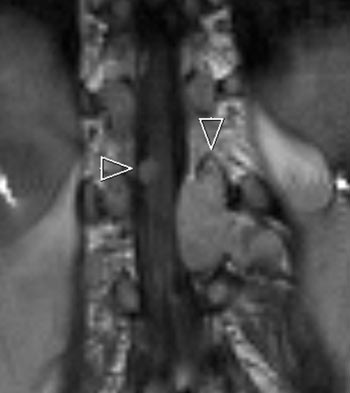

Det kliniske bildet ved nevrofibromatose type 2 domineres av symptomer og tegn som skyldes utvikling av multiple svulster. Om lag 95 % av personer med sykdommen vil utvikle bilateralt vestibularisschwannom (1), som vist i figur 1. Hvorfor vestibularisdelen av 8. hjernenerve er predileksjonssted, er ikke kjent. Schwannomer på andre hjernenerver og på perifere nerver, intrakraniale og intraspinale meningeomer, ependymomer og lavgradige gliomer er andre svulster assosiert med sykdommen (4). Spinale svulster, som vist i figur 2, kan påvises hos 80 – 90 % av personer med nevrofibromatose type 2 (4). Imidlertid vil kun om lag 30 % av disse ha behov for spinal kirurgi (9).